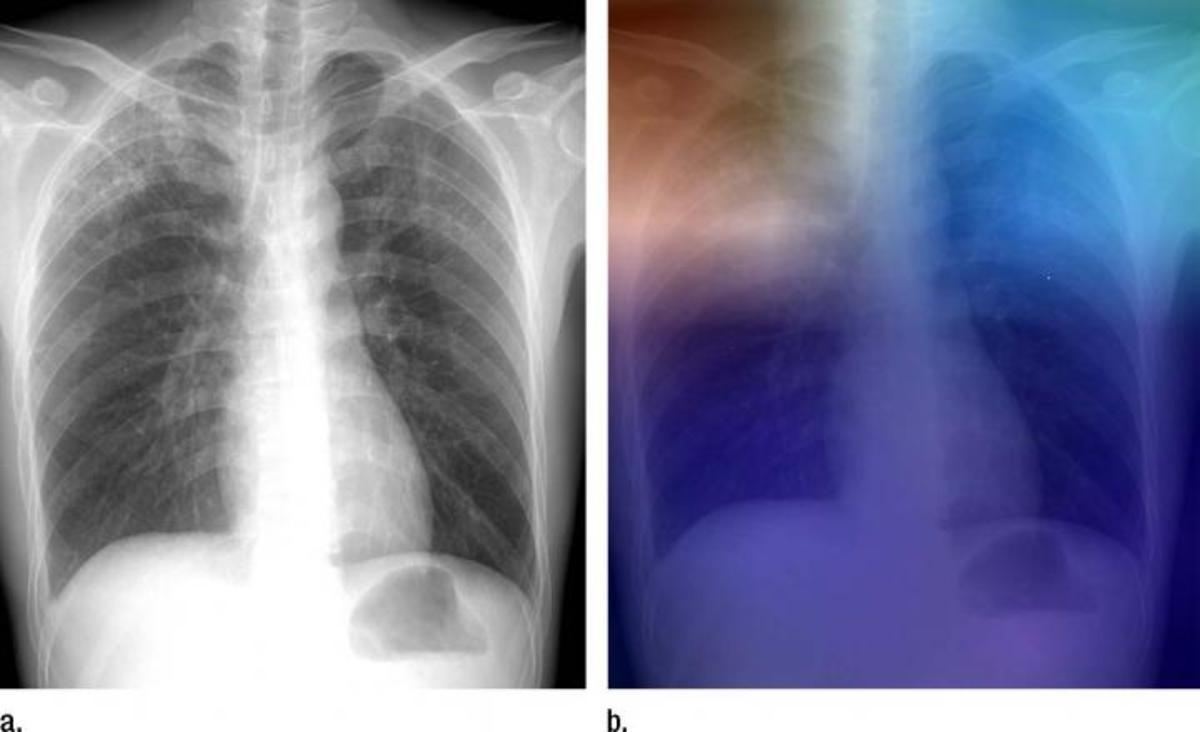

(Α) Ακτινογραφία του θώρακα παρουσιάζει την αδιαφάνεια του άνω λοβού με παθολογική ανάλυση αποδεδειγμένης ενεργής φυματίωσης. (Β) Η ίδια ακτινογραφία θώρακος με επικάλυψη θερμικής απεικόνισης μετά την ανάλυσή της μέσω του συστήματος UserNet-TA. Οι περιοχές κόκκινου και γαλαζοπράσινου στους άνω λοβούς αντιπροσωπεύουν περιοχές που ενεργοποιούνται από το βαθύ νευρικό δίκτυο. Το σκούρο μοβ φόντο αντιπροσωπεύει περιοχές που δεν ενεργοποιούνται. Αυτό δείχνει ότι το σύστημα επικεντρώνεται σε τμήματα της εικόνας όπου υπάρχει η ασθένεια (και οι δύο άνω λοβοί).